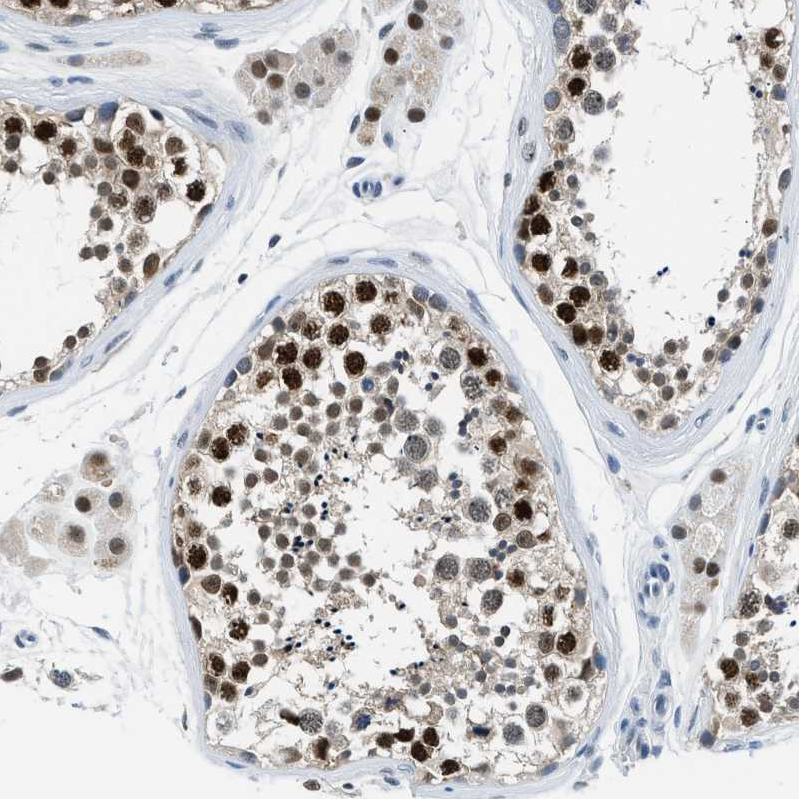

Immunohistochemical staining of human kidney shows strong nuclear positivity in cells in tubules.